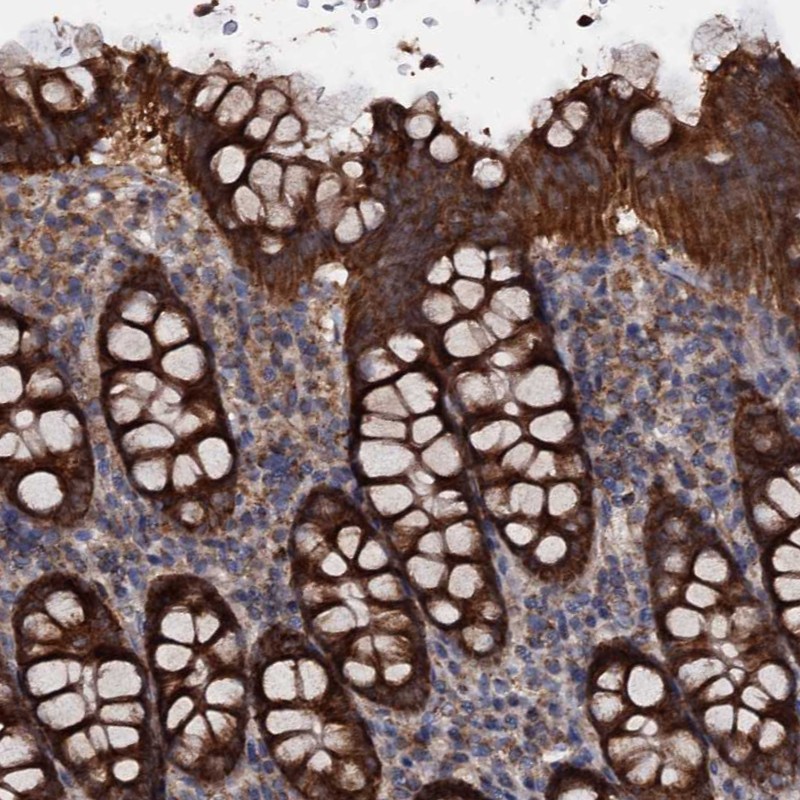

Immunohistochemical staining of human colon shows strong cytoplasmic positivity in glandular cells.